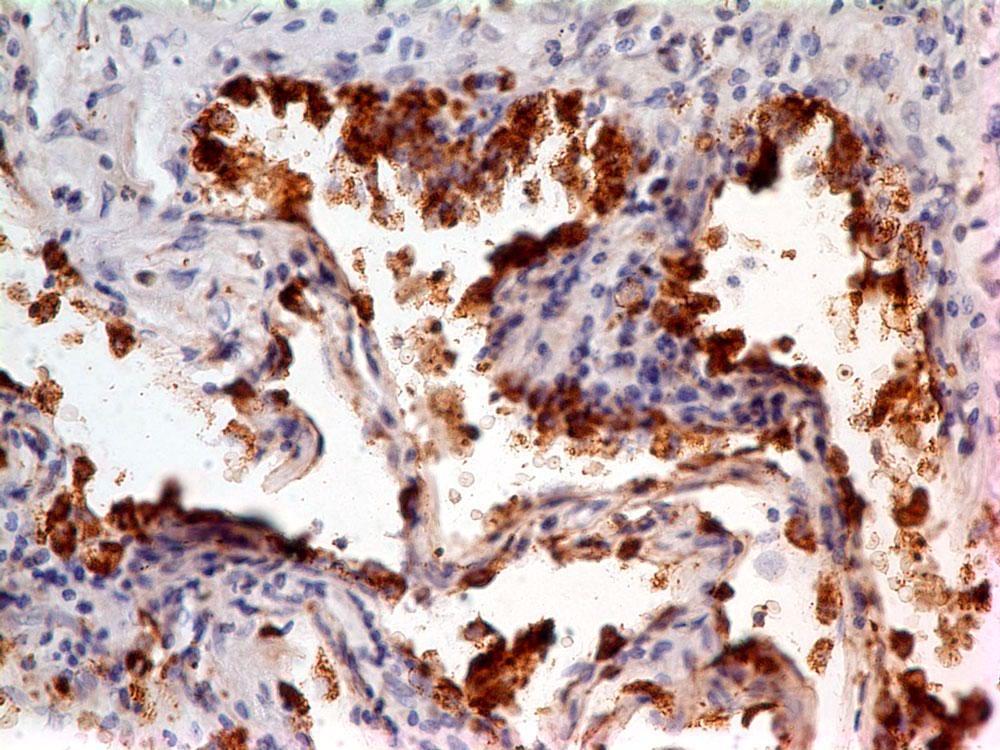

Supportive validation

- Submitted by

- ABEOMICS Inc. (provider)

- Main image

- Experimental details

- Immunohistochemical analysis of Napsin in Lung Adenocarcinoma tissue using Napsin antibody (Clone: ABM4H60) at 5 µg/ml.